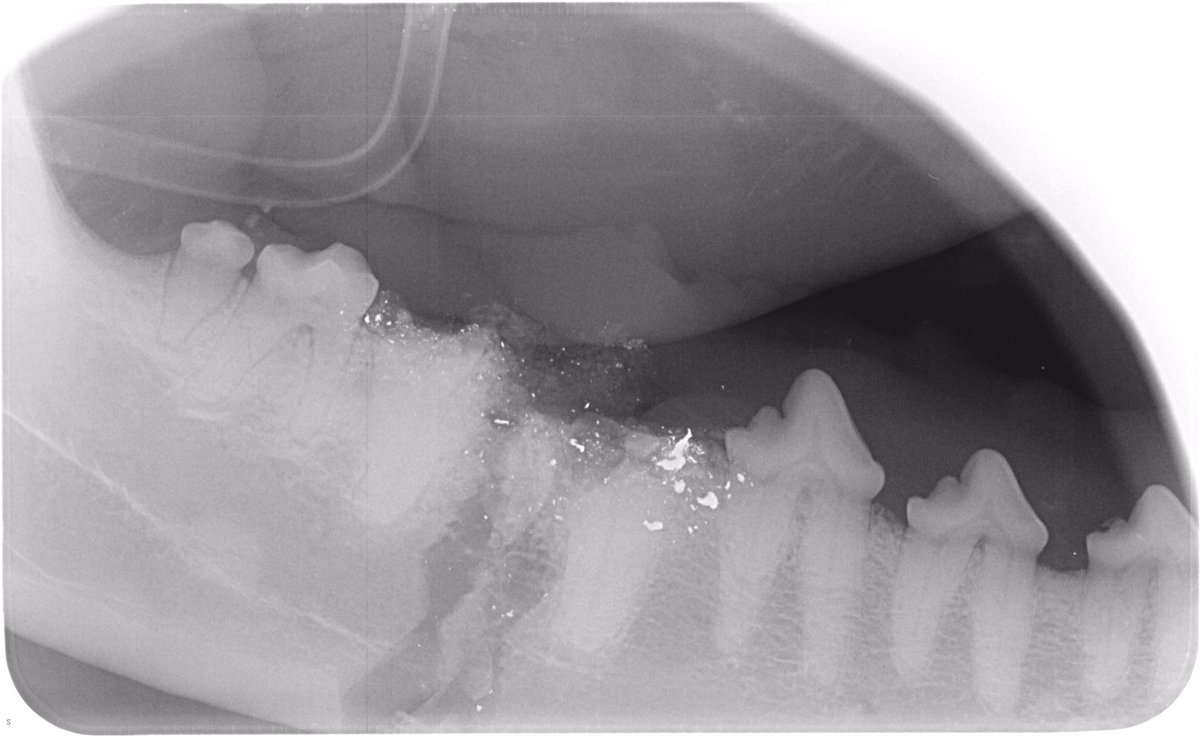

Nous avons commencé par faire des radios, qui ont montré de nombreux morceaux de métal incrustés dans sa gueule. Nous avons dû l'opérer pour retirer les fragments de dents et de métal. Sa langue a presque été coupée en deux, mais pas entièrement.